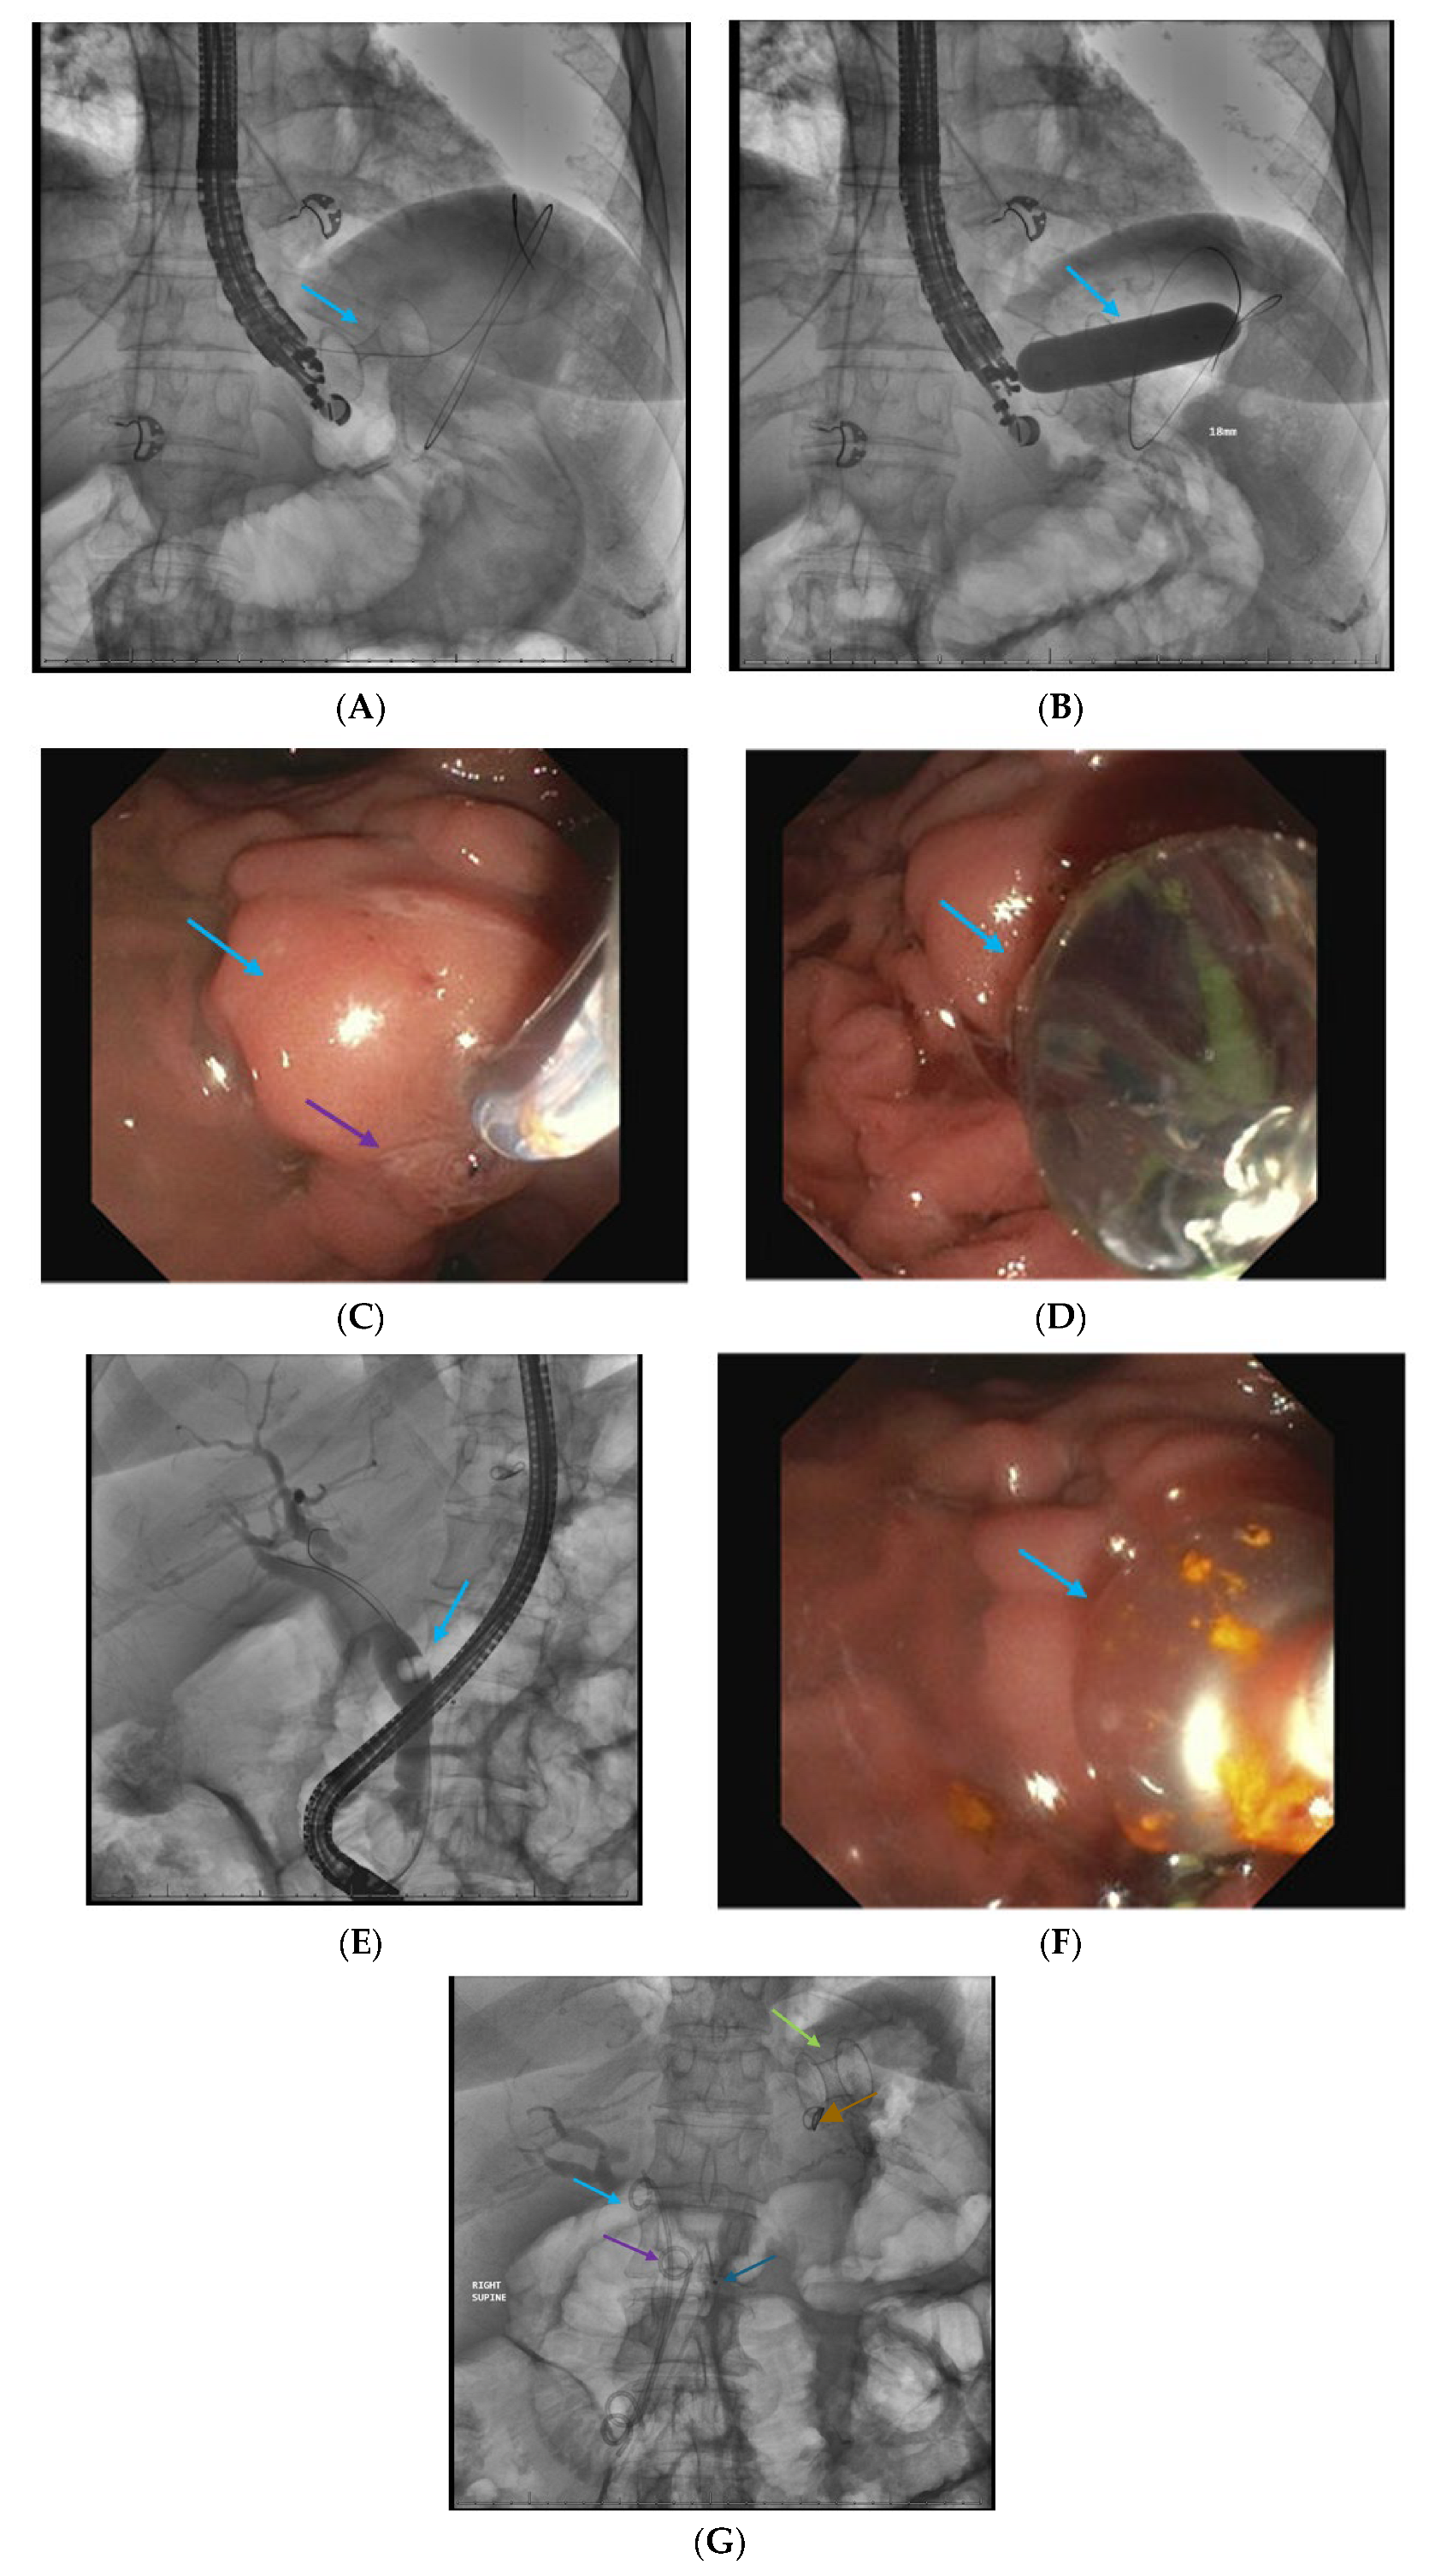

2.4. Endoscopic Ultrasound-Guided Techniques for Walled-Off Pancreatic Necrosis (WON)

2.5. Direct Endoscopic Necrosectomy

2.6. Dual Modality Drainage